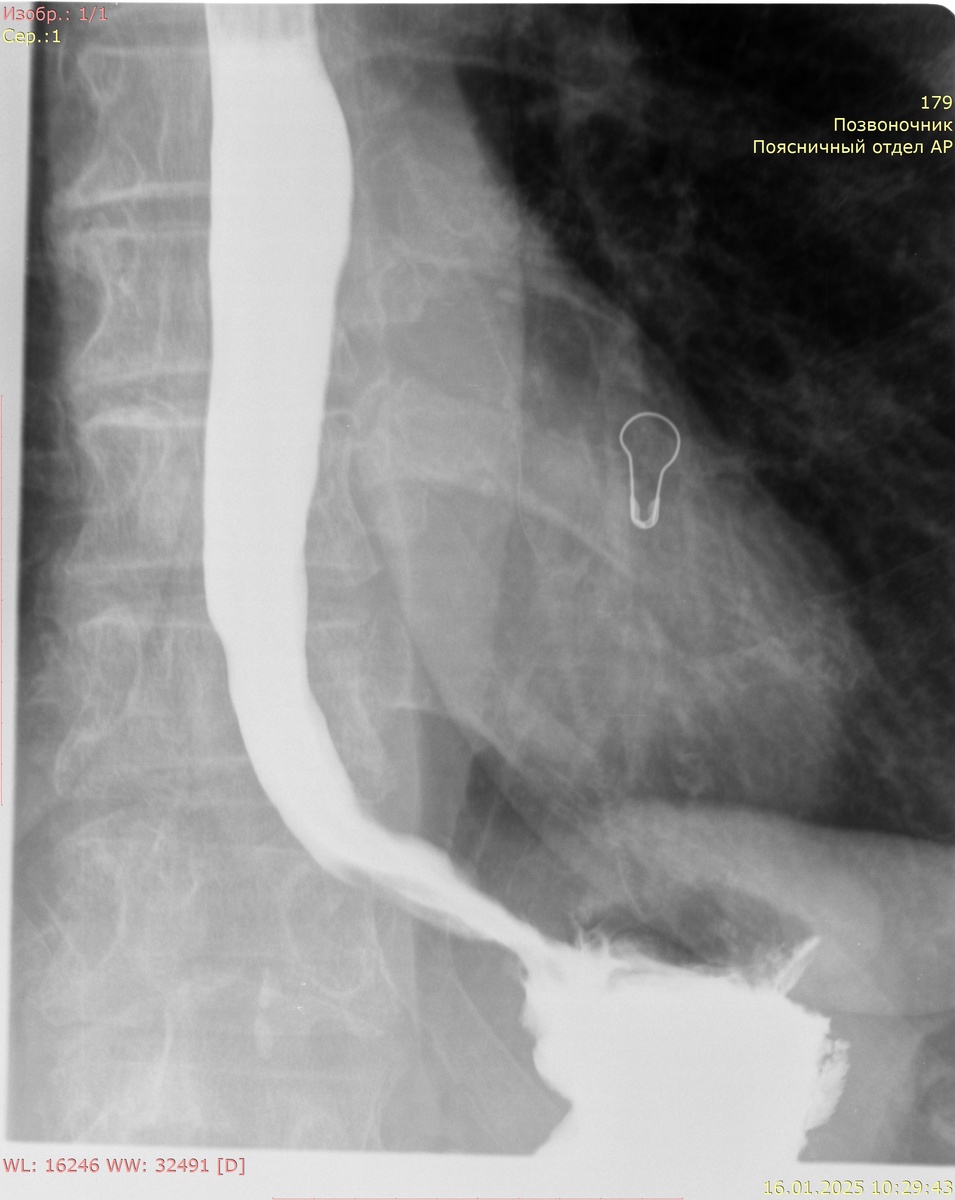

Процедура начинается с того, что пациенту предлагают выпить раствор бария. Барий сульфат, используемый в качестве контрастного вещества, не впитывается в организм и надежно обвивает слизистую оболочку органов, что позволяет увидеть их контуры при рентгеновской съемке. Благодаря этому исследованию можно диагностировать различные патологии, включая воспаления, опухоли и язвы. Эта процедура достаточно безопасна, и побочные эффекты возникают крайне редко, однако существуют противопоказания, такие как аллергия на барий или подозрения на непроходимость кишечника.

Пищевод и вход в желудок (кардия)